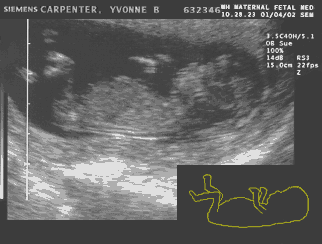

The MY baby takes a test — January 4th — 12 weeks

MY's looking good at 12 weeks Matt: The last two weeks were kind of fun. Luke or Kyla and I have had many conversations but so far they have been rather one sided. Yvonne has gotten in some really good runs and did not complain about nausea near as much. However there has been more complaints (from her) revolving around the three B’s — Butt, Belly, and Boobs. Make that the 4 B’s — BIG! She walks into the room stark naked and says things like, “my boobs are about to explode” butt (sic;-) enough of that! The ultrasound was again so cool I can’t even put it into words. Turns out that little animation at the top of the page is not too far off. The whole time the nurse was trying to take measurements arms were flying and legs were kicking. It was incredible! At one point right when an important measurement was about to be taken the MY baby turned it’s back to us. It was so funny! At any rate, all the measurements came out fine. Of course when it came time to record the video the MY baby seemed to take a nap. However the nurse jiggled the transducer and sure enough kick, wiggle, wiggle, turn the MY baby will soon be on DVD:-)

Yvonne: Phew!!!!!! I can’t believe we reached 12 weeks. It felt more like 12 years! The nausea is almost all gone but is being promptly replaced by a vicious appetite:-) I started watching the amount of food I eat and try not to get carried away using the pregnancy as an excuse to overeat. The plan is obviously NOT to starve the baby, but make the mom look somewhat human when this is all said and done! I feel like a cow — no exaggeration and the funny part is that I did not even gain the “big” weight yet. My breasts — can I talk about my breasts here? Just checking — they are HUGE! Melons come to mind. I look for tight bras to run in which is not hard given that everything I currently own is tight. I think I will go shopping for more comfortable underwear tomorrow… I can still fit in most of the current ones, but high school days come to mind when I try to put them on and it feels like trying to squeeze into a pair of jeans 2 sizes below your size (girls, remember that!) Today I actually had to put a pair back:-( Luke or Kyla seem to be doing fine and passed the first big test. I am sure that a future boyfriend/girlfriend/husband/wife will pay big money to see the video we got — it is so cute!!!